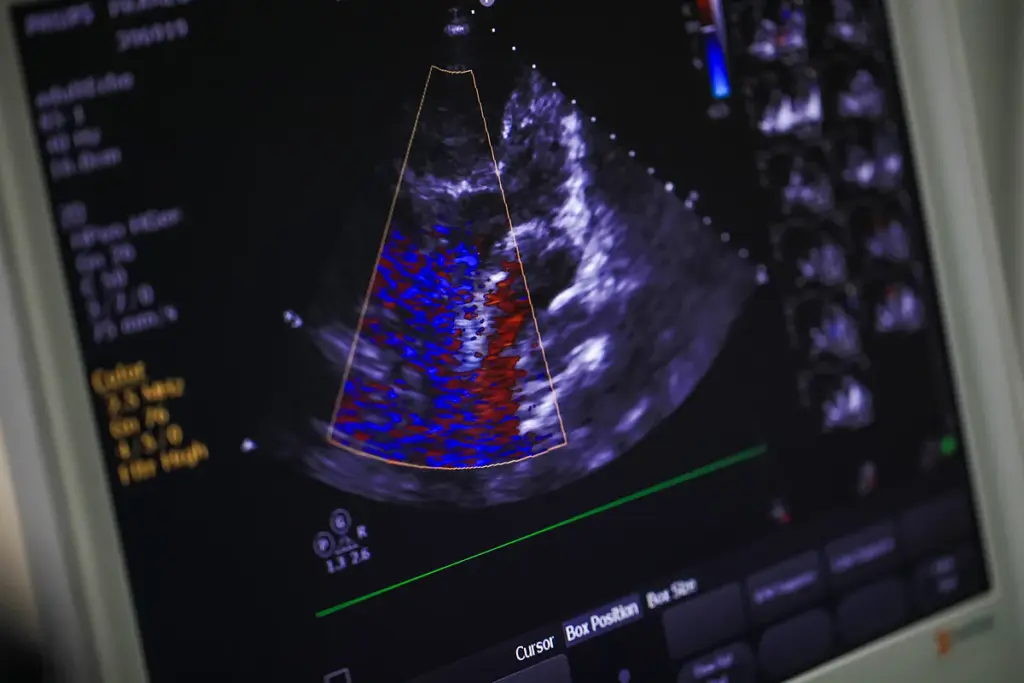

How FFR Works in Practice

It’s important to know how Fractional Flow Reserve (FFR) works in cardiology. FFR is a part of a test called diagnostic cardiac catheterization. It shows the pressure difference across a coronary stenosis.

FFR Calculation Methods and Technology

FFR is key in deciding treatments. It’s calculated by comparing pressures before and after a blockage. This shows how much a blockage affects heart blood flow.

Mathematical Principles Behind FFR

FFR math is simple. It’s the ratio of blood flow through a blocked artery to normal flow. This is done by comparing the pressure after the blockage to the aortic pressure when blood flow is at its highest. The formula is: FFR = Pd / Pa, with Pd being the pressure after the blockage and Pa the aortic pressure.

Accurate FFR calculation is vital. It tells doctors if a blockage is serious enough to cause heart problems. This helps decide if a patient needs a procedure to fix the blockage.

Pressure Wire Systems and Equipment

Pressure wire systems are essential for FFR tests. They have a guide wire with a pressure sensor at the tip. This wire goes through a catheter to the heart artery. It measures pressure after the blockage, while another part measures aortic pressure.

Today’s pressure wires are advanced. They can navigate through the heart’s complex paths. They give accurate pressure readings in real-time.